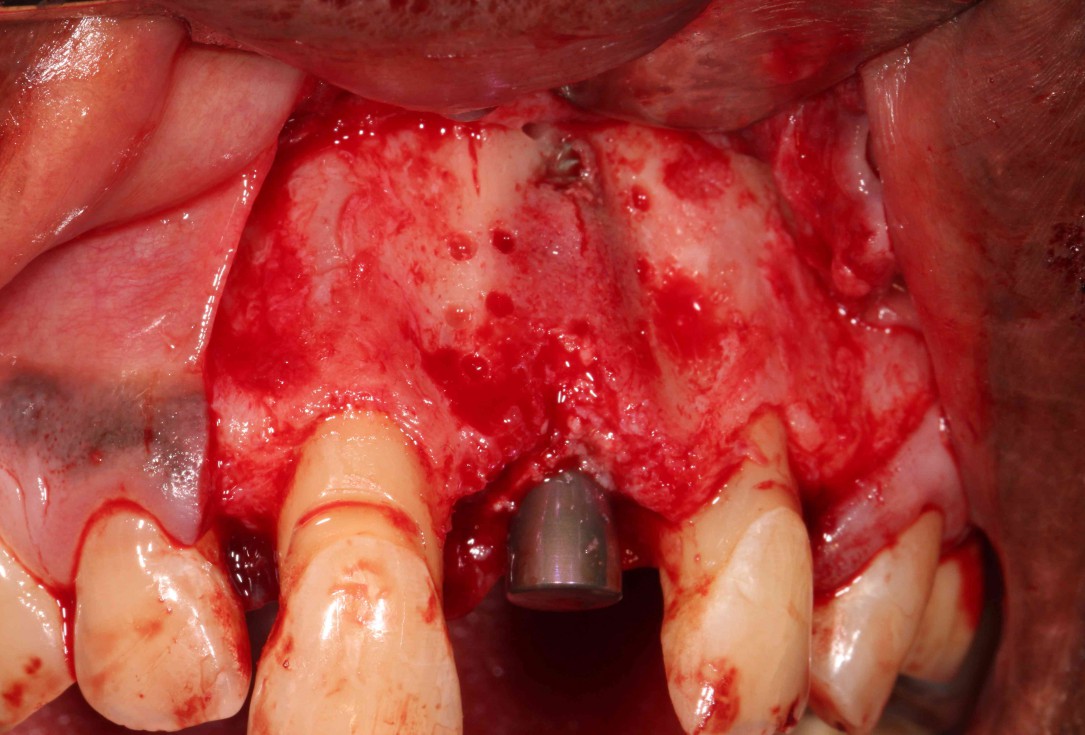

03/19 - Placement of a Straumann 4.1 x 14 mm Roxolid SLA BLT implant within the prosthetic envelop after removal of granulation tissue

GBR with cerabone® and Jason® membrane in the front tooth region - Dr. H. Maghaireh